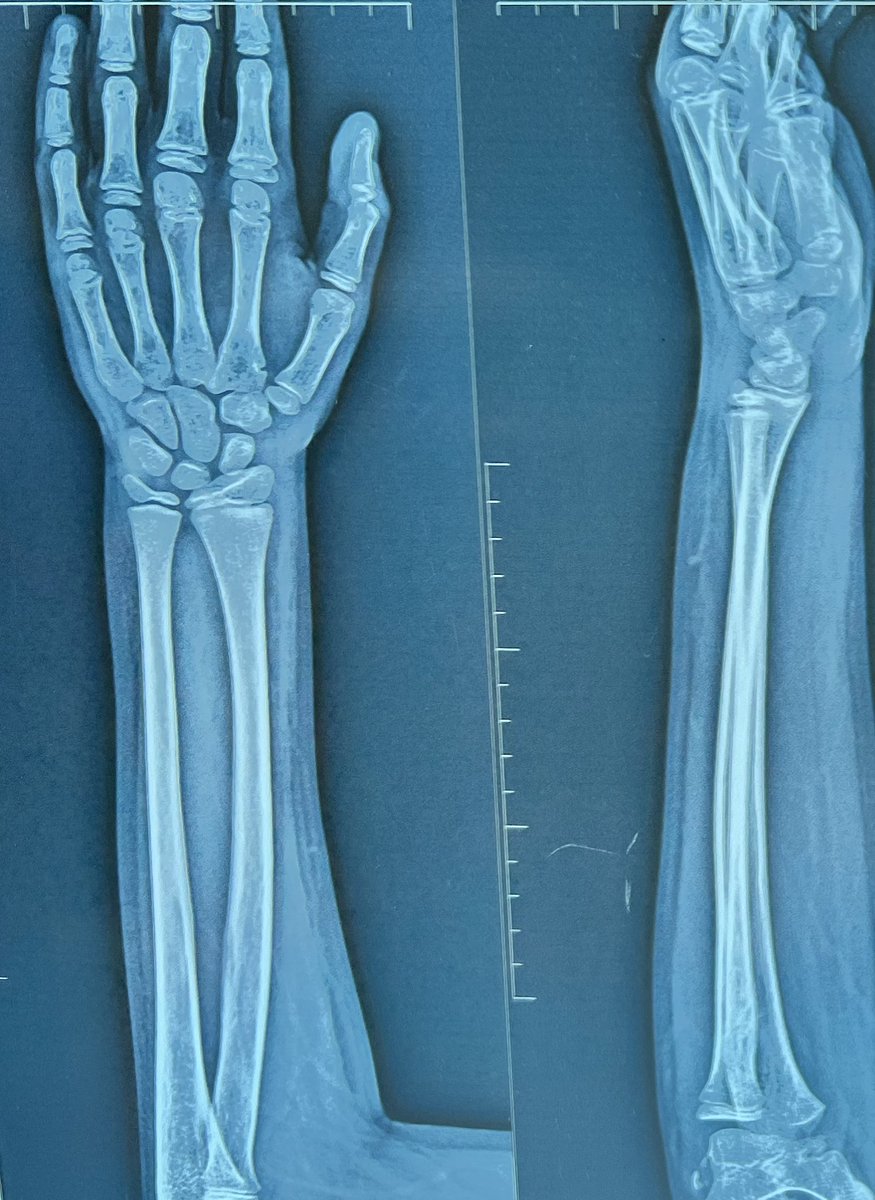

تم استئصال العظام الميتة و تركيب اسمنت طبي مؤقت لحين التأكد من انتهاء الصديد ثم عمل ترقيع للعظم.